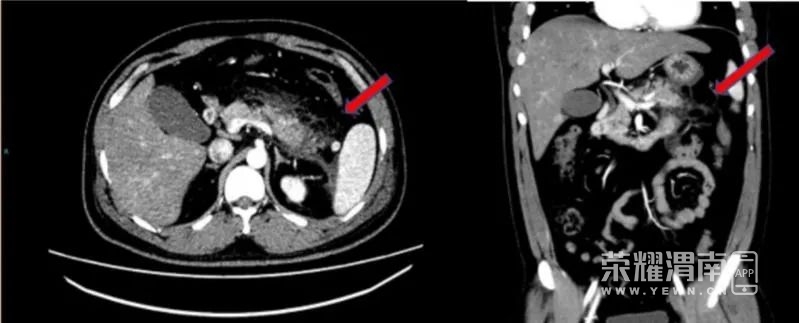

当时,小于腹痛难忍、大汗淋漓、面色苍白、呼吸急促。急诊科杨桂萍医生紧急进行血液化验,发现血液在试管中明显分层,上层悬浮着油脂样物质,竟然是乳糜血! 检验科的医师通过机器质检,结合腹部CT,确定小于得了急性坏死性胰腺炎和2型糖尿病伴酮症酸中毒。 腹部增强CT提示胰腺尾部肿胀,胰腺周围脂肪间隙模糊,多发斑片状、条索影。红色箭头示胰腺脂肪间隙。 小于血液置换过程中刚抽出的血为粉红色。 “患者以前没有糖尿病史和高脂血症病史,这次病发才知道自己身体的真实状况。”中山六院消化内科郅敏主任医师表示,身高168厘米的小于,体重达85公斤。他的血液检验中有多项指标异常,甘油三脂高达44.49毫摩尔/升,是正常人的近25倍,胆固醇是正常人的近3倍,血糖维持在11毫摩尔/升以上,并多次高于15毫摩尔/升。郅敏主任医师立即联系该院重症医学科主任杨春华主任医师进行会诊。杨春华主任建议立即进行床旁血液置换进行降脂治疗。